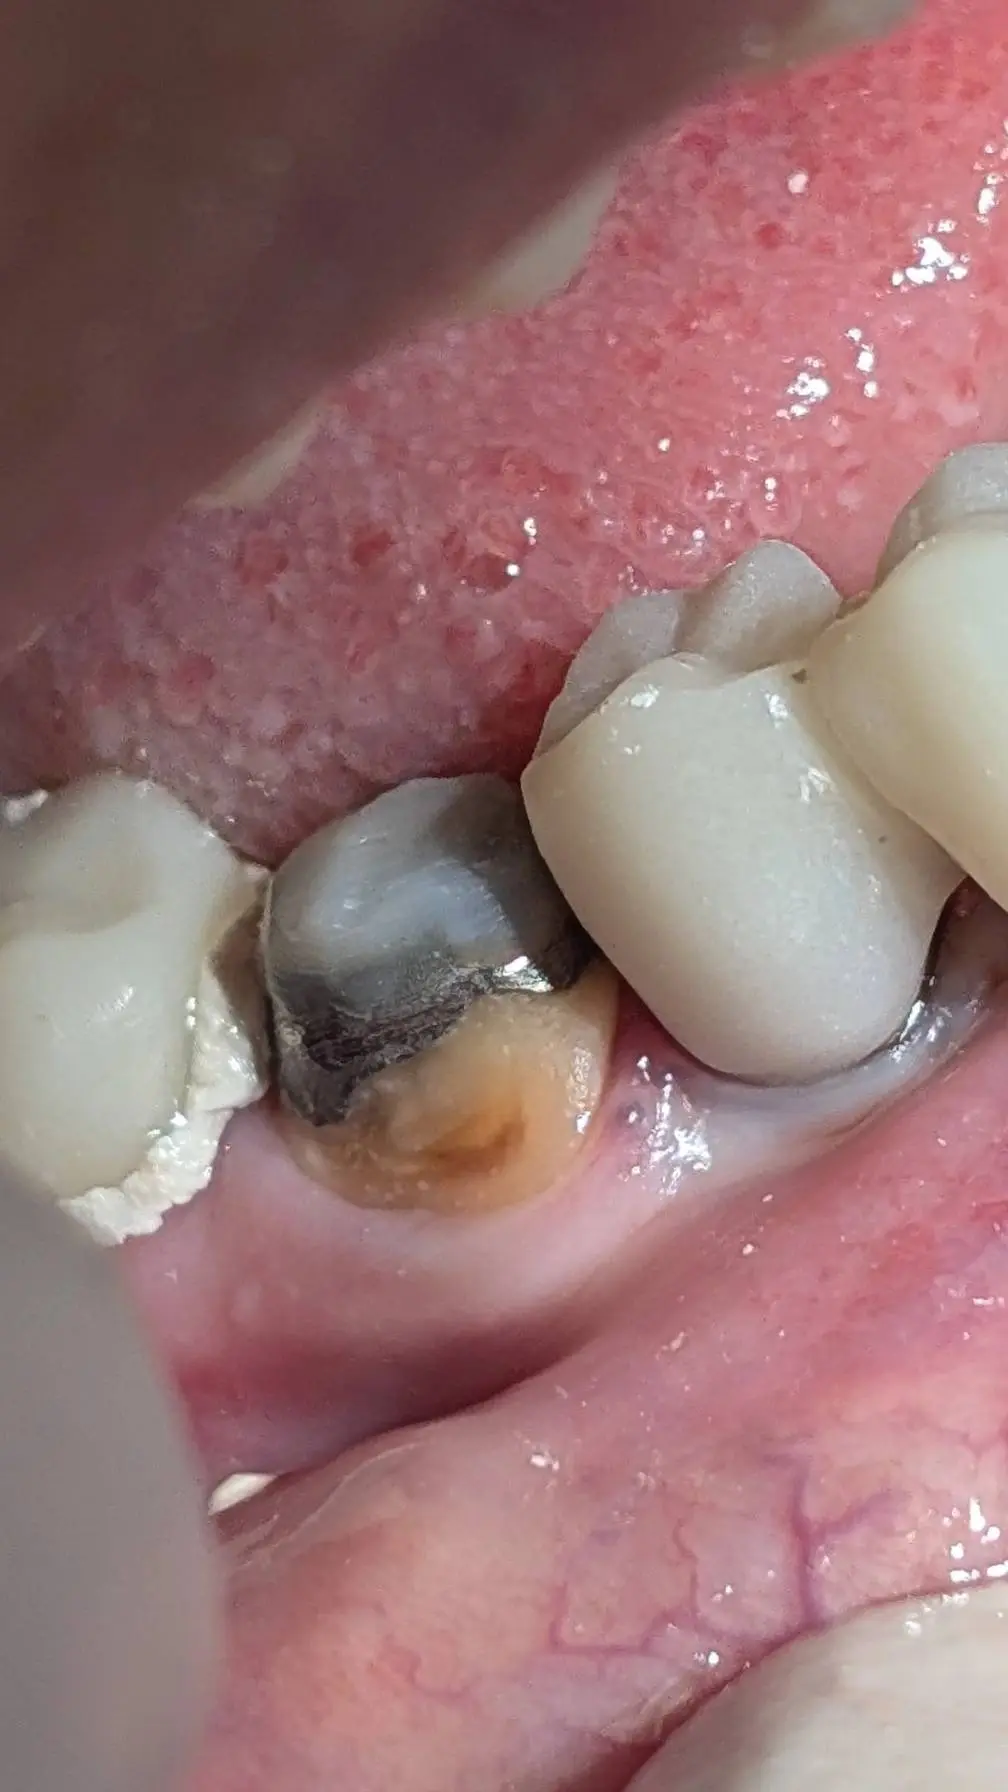

باند کامپوزیت به پست و کور فلزی

در بیماری که عکسش گذاشته شده در حال بازسازی وسیع دو فک بودیم در جلسه ی قبل همه ی پست کورها سمان شدند و دندانها اسکن شد تا این جلسه روکشهای موقت تحویل بیمار شوند

اما نکته اینجا بود که در وضعیت موجود در جلسه ی قبل که همه ی دندانها پست و کور بودندو نبود استاپ خلفی حتی به شکل موقت،تماس سنگین روی دندان و پست و کورهای قدامی بود و احتمال شکست این دندانها در فاصله ی آماده شدن روکشهای موقت زیاد بود

برای جلوگیری از این مساله به شکل موقت روی دندانهای خلفی منتخب در VD مناسب کمی کامپوزیت باند شد تا در فاصله زمانی آماده شدن روکش های موقت به دندانهای قدامی فشار وارد نشود و از آنها محافظت شود

برای باند کامپوزیت به کور فلزی از روش باند به فلز که قبلا در پادکستها توضیح داده شده استفاده شد